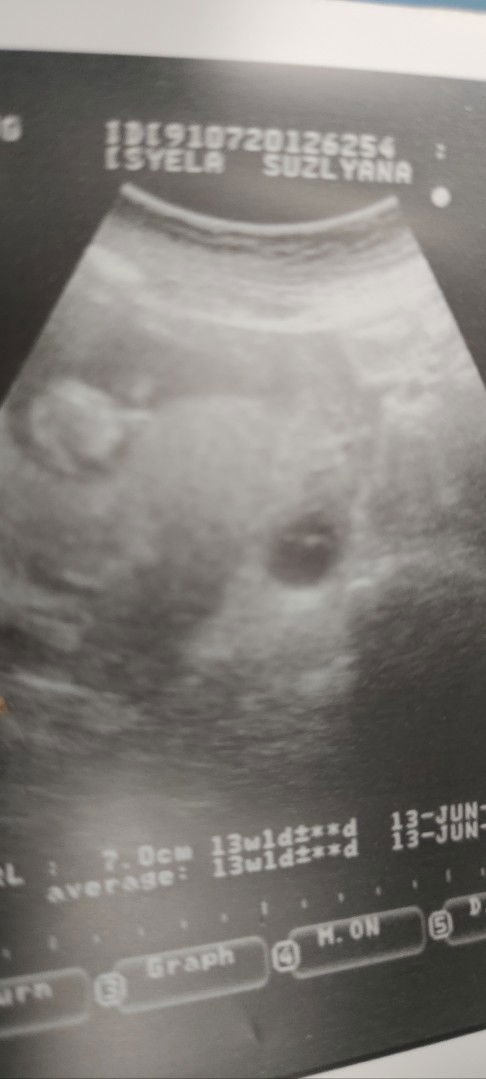

Kembar tp 1 kantung xjadi

Sy nak tnya ibu2 yg perna alami kesb mcm sy boleh kongsi tak.. atas tu gmbar janin..bawah tu ada mcm kantung(sbb dr pun tak pasti lg)mgkin kembar tak jadi..repeat scan 13/12 ni tp sy agak takut.. #ingintahu #pleasehelp #seriusnanya